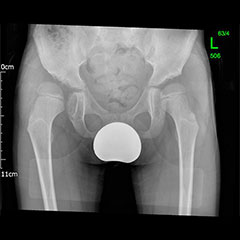

Young Adult Hip Preservation Surgery

'Hip Preservation Surgery' is a non-specific term that refers to surgical methods aimed at preserving your own hip and essentially avoiding a hip replacement. Ideally, in order to be a candidate for this type of surgery, the vast majority of the cartilage in the joint has to still be intact. This means that, ideally, the hip shouldn't have any arthritis, or at the very least minor wear. Unfortunately, in some patients, too much cartilage has been damaged. In these cases, hip preservation is not an option and a consultation with a hip replacement surgeon is required.

Hip preservation - before

Hip preservation - after

Osteotomies around the hip

Surgeries on the hip socket side are called ‘acetabular osteotomies’ or ‘pelvic osteotomies’ and of these the PAO (periacetabular osteotomy) is the most common type for young adults. This is also called the Ganz or Bernese osteotomy because it was developed by Professor Ganz in Berne, Switzerland. Surgery on the top of the thigh bone (just below the hip joint on the ball side of the joint) are called ‘femoral osteotomies’. These may be varus (tilting the hip in) or valgus (tilting the hip out), or an isolated trochanteric procedure, depending on the precise aim of surgery. The conditions that can be treated with osteotomies around the hip are as follows: